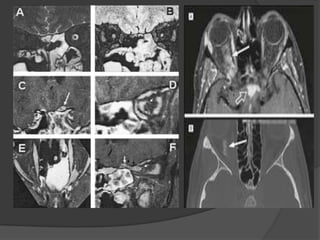

 MR imaging:

 Better shows intracranial

extent.

 Coronal and axial thin-

section of T1, T2 and fat

suppression.

 Screening examination of

the brain.

 Post contrast T1 and fat

supp. images.

Optic Nerve Glioma:

 Fusiform or less commonly

eccentric globoid,

enlargement of optic

pathway.

 iso- to hypointense to

the optic pathway on

TIWIs.

 slightly hyperintense on

T2WIs.

 Areas of hemorrhage or

calcification are rare.

 Enhancement with IV

gadolinium is variable.

 Posterior extension may

at seen only at post IV

contrast imaging.

 Isolated optic nerve

glioma more common in

patients with NF1.

 Optic pathways

extension more

common in children

without NF1.

Optic Nerve Glioma: MR imaging:  Better shows intracranial extent.  Coronal and axial thin- section of T1, T2 and fat suppression.  Screening examination of the brain.  Post contrast T1 and fat supp. images.

Optic Nerve Glioma: Fusiform or less commonly eccentric globoid, enlargement of optic pathway.  iso- to hypointense to the optic pathway on TIWIs.  slightly hyperintense on T2WIs.  Areas of hemorrhage or calcification are rare.

Optic Nerve Glioma: Enhancement with IV gadolinium is variable.  Posterior extension may at seen only at post IV contrast imaging.  Isolated optic nerve glioma more common in patients with NF1.  Optic pathways extension more common in children without NF1.